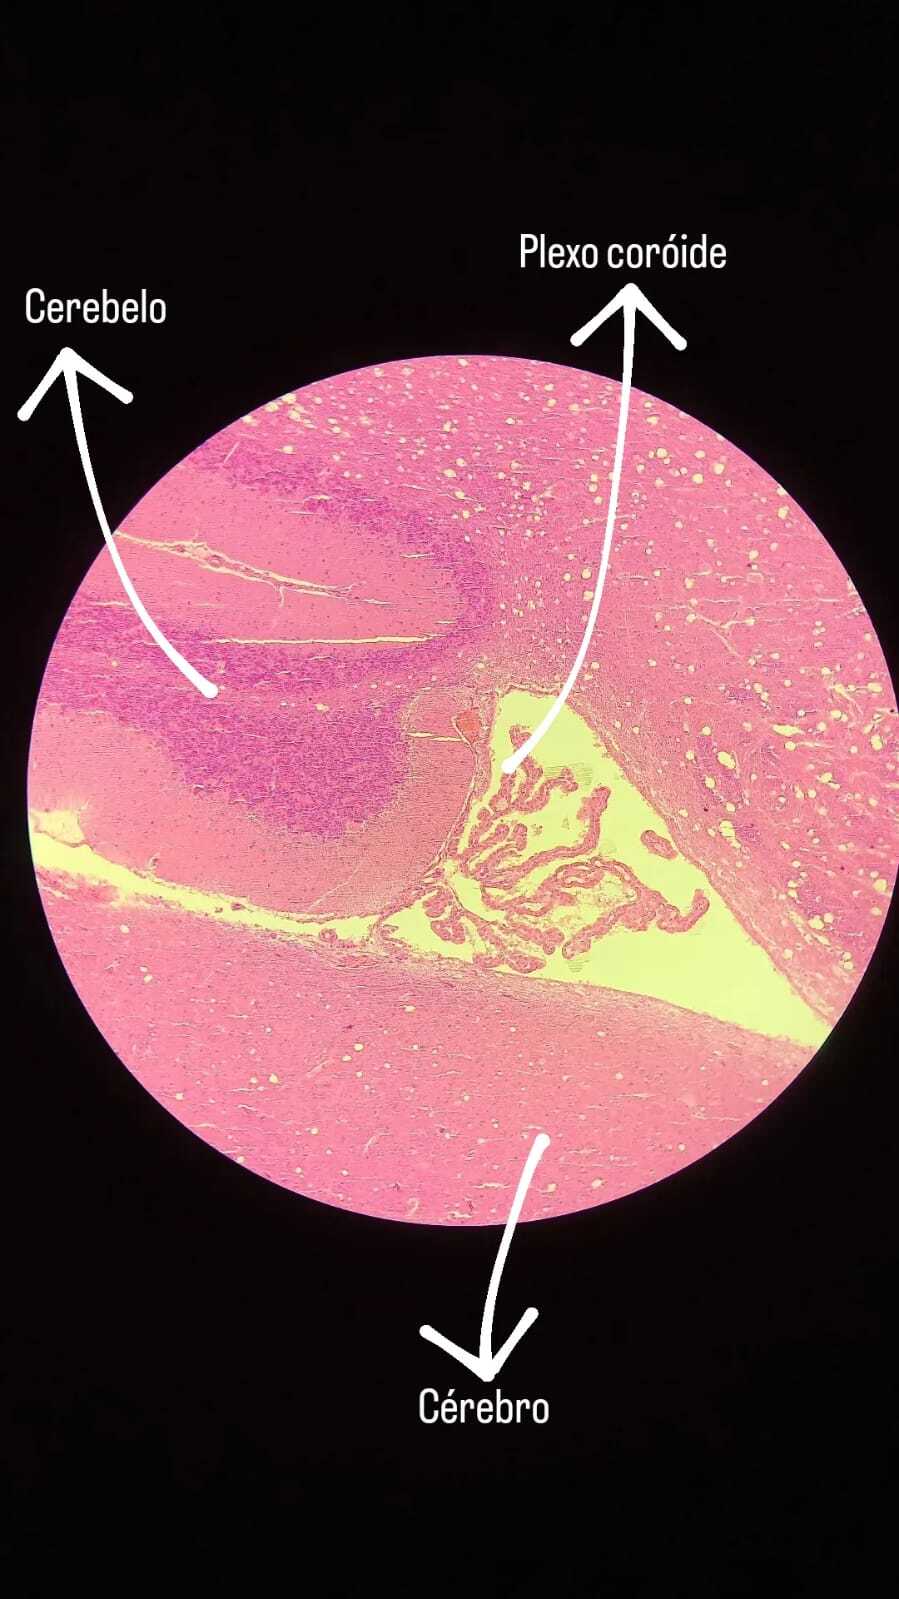

9

Q

Identifique;

Órgão:

Quais estruturas te auxiliaram até a conclusão:

A

Órgão: Cérebro e cerebelo

Quais estruturas te auxiliaram até a conclusão: Cerebelo (camada molecular, camada central, camada granular), Cérebro (Anterior), Plexo coróide.